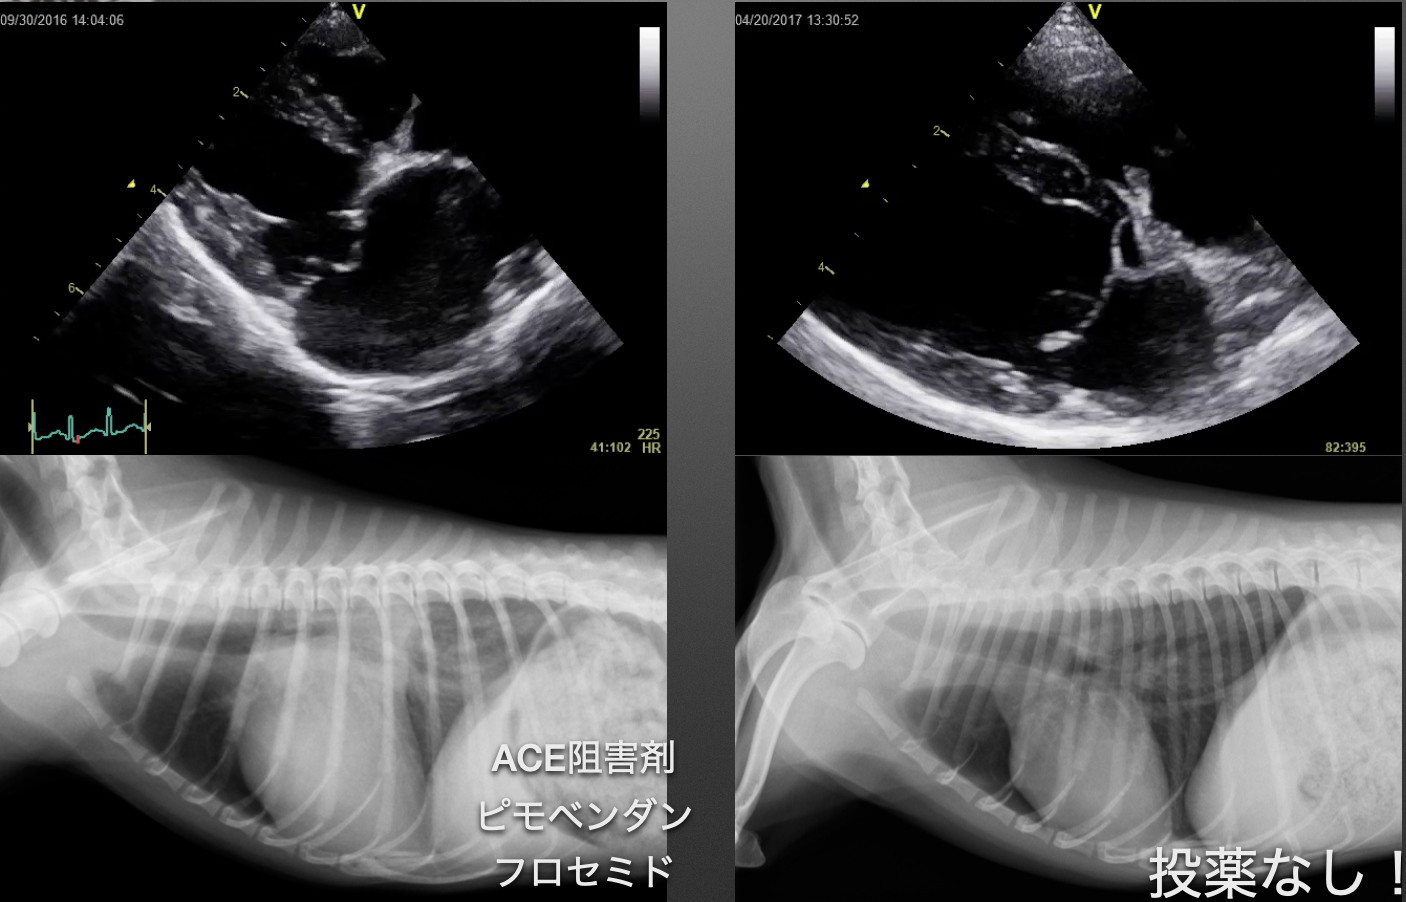

心臓の手術がうまく行くと、僧帽弁逆流はほとんどなくなり、心拡大は良化し苦しかった肺水腫の症状は消失します。逆流がほとんどなくなった場合にはこれまで飲んでいた沢山の薬は必要なくなる場合が多いです。(100%ではございません。)

しかし一方で、心臓を一度停止させて手術を実施するため色々な合併症が起きることもあり、全ての命が助かるわけではありません。そういったリスクを乗り越えて退院したわんちゃんたちは、元気になり苦しんでいた咳も消失しその後の人生が豊かなものになると考えます。

心臓病は全て手術で治すわけではなく、現在は内科の治療が第一選択であり、手術が必要かどうかはよく見極めないといけません。退院して「以前よりずっと元気になりました!」「咳もなくなり、とても楽そうにしている」など喜びの声を聞くと手術やって良かったなと思える瞬間となります。